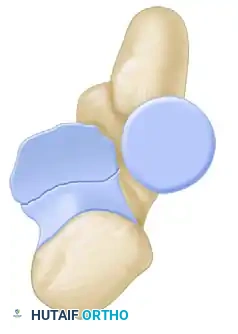

Radial head fractures rarely occur in isolation when subjected to high-energy trauma. They are frequently a component of the "terrible triad" of the elbow (radial head fracture, coronoid fracture, and elbow dislocation). Understanding the associated coronoid pathology is paramount for restoring anterior stability.

The Coronoid Fracture Classification (O’Driscoll et al.) categorizes these injuries based on the anatomic location and fragmentation pattern, which directly dictates the surgical approach and fixation strategy.

Type I: Tip Fractures

* Subtype 1: ≤ 2 mm coronoid bony height (i.e., a capsular flake fracture).

* Subtype 2: > 2 mm coronoid height.

Type II: Anteromedial Facet Fractures

* Subtype 1: Anteromedial rim.

* Subtype 2: Anteromedial rim + tip.

* Subtype 3: Anteromedial rim + sublime tubercle (± tip).

Type III: Basal Fractures

* Subtype 1: Coronoid body and base.

* Subtype 2: Transolecranon basal coronoid fracture.